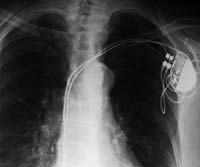

Крошечные устройства, предназначенные для спасения жизни пациентов, имплантируются в грудную клетку и соединяются проводами с сердцем. В случае хакерской атаки неравномерная подача напряжения приведет к тому, что сердечная мышца начнет хаотично сокращаться, вместо того чтобы равномерно перекачивать кровь.

С помощью этих нехитрых средств группа исследователей смогла получить доступ к так называемому «имплантируемому кардиовертеру-дефибриллятору», считать конфиденциальную информацию о пациенте, нарушить нормальное функционирование устройства и даже запрограммировать его таким образом, чтобы оно время от времени выдавало достаточно сильный электрический разряд.